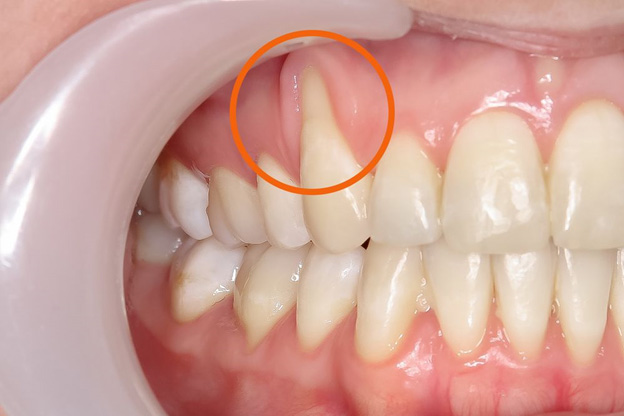

Visible Tooth Roots: One of the primary signs is the exposure of tooth roots as the gum line recedes

Longer Teeth: Teeth may appear longer than usual due to the recession of the gums.

- Misalignment of tooth structure.